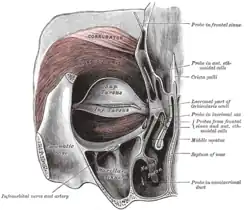

Seção horizontal das cavidades nasais e orbitárias. Óculos orbicular esquerdo, visto por trás.

Óculos orbicular esquerdo, visto por trás. Ossos zigomáticos.